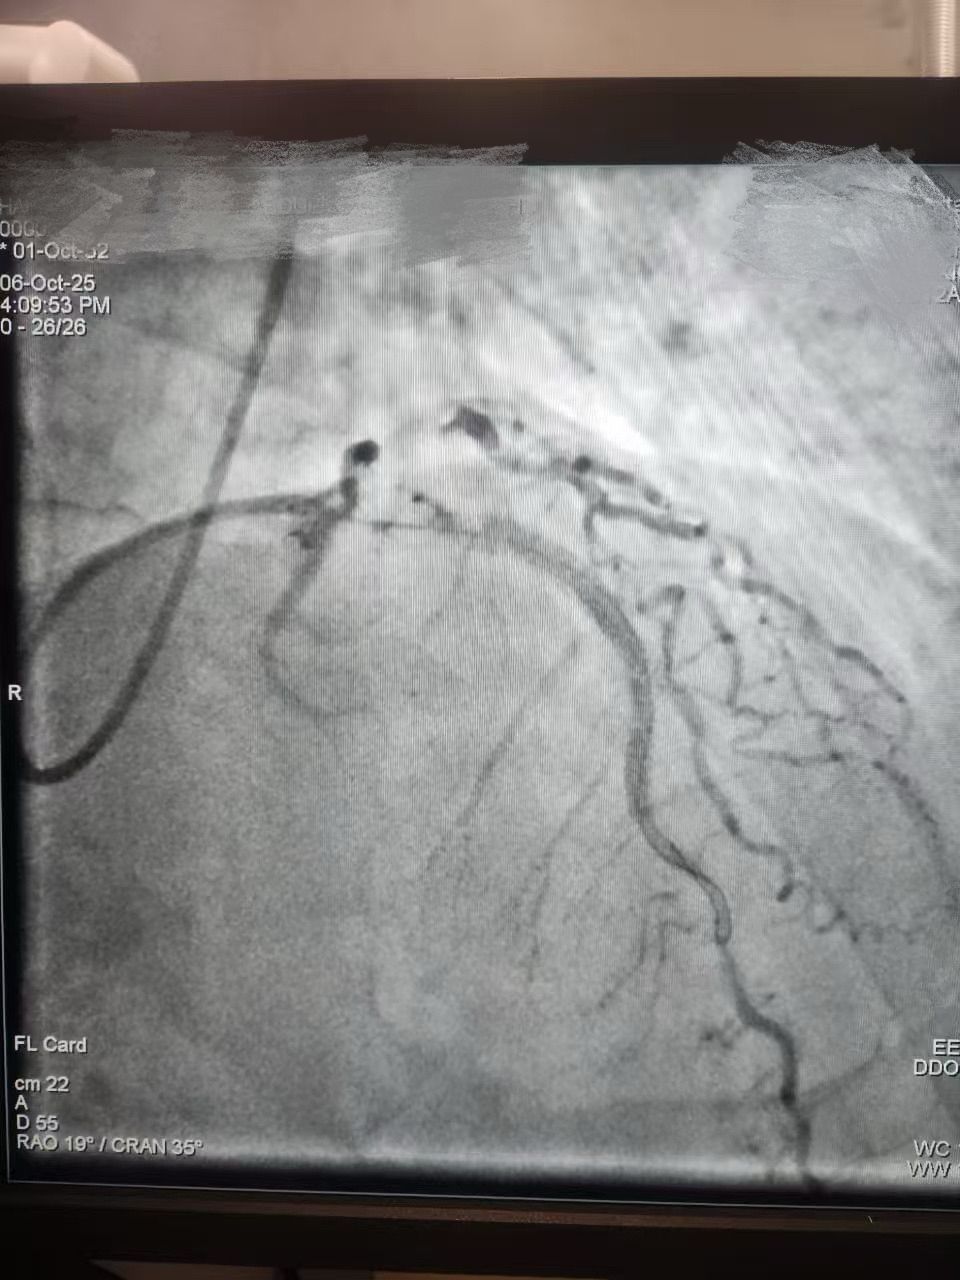

We are proud to share a successful clinical case from HMS Mirdif Hospital, UAE, where Dr. Mohamed Houcem Amiour and his exceptional Cath Lab team — Ambily Mathew, Aswathy S Babu, Geethanjali Rema Suresh, and Mathew Philip — successfully performed a PTCA to the LAD using Lepu Medical's Vesscrack Coronary IVL Balloon System.

To achieve optimal lesion preparation and stent expansion, the team skillfully combined Rotablator with Lepu's IVL, ensuring precise and effective calcium modification.

It demonstrates how Lepu's IVL technology delivers powerful calcium modification performance, supporting physicians in achieving safe and efficient outcomes in complex coronary interventions. A huge thank-you to Dr. Amiour and his incredible Cath Lab team for their trust in Lepu Medical.